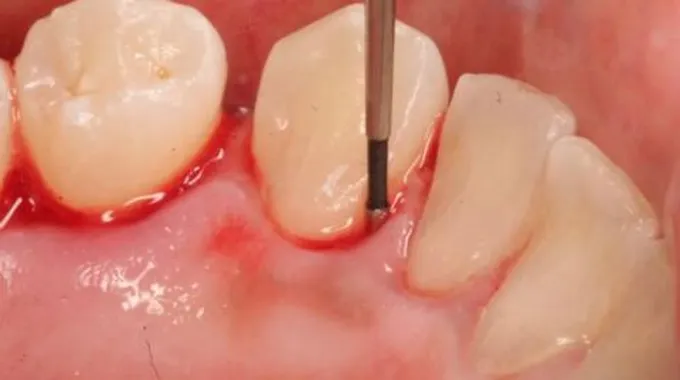

- نزول الدم أثناء تنظيف الأسنان و تنظيف اللثة.

- نزول الدم عند تناول اي من المواد الغذائية الصلبة مثل التفاح أو أي نوع أخر من الفاكهة، و تحدد نسبة الإلتهاب بالفم على قدر النزيف.